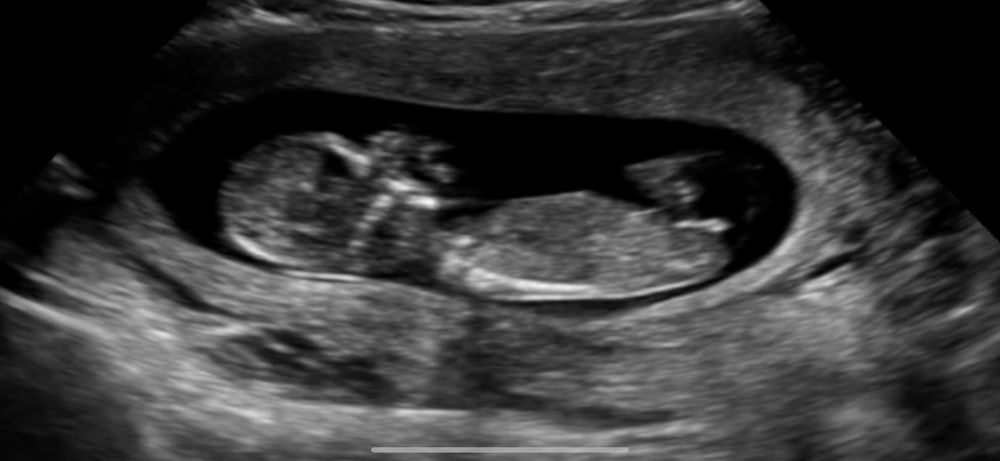

Мне по половому бугорку видится девчуля… а вам?))

Я вообще подумала бы пацан по первому снимку но у нас 3 точно такой же и нам сказали девочка на 90%

Яна, врач в начале узи тоде сказал что похоже на мальчика 😂 ( как раз там где 1 фото и стрелочка))) а в конце узи сказал, нет, я меняю мнение - это скорее всего девочка. Но я думала он мог изменить мнение тк в процессе узи узнал что у нас уже 2 сына 😂 Решил мне надежду оставить 😂

Я думаю девочка, у меня в дневнике есть фото нашего скрининга похожи бугорки 🤞